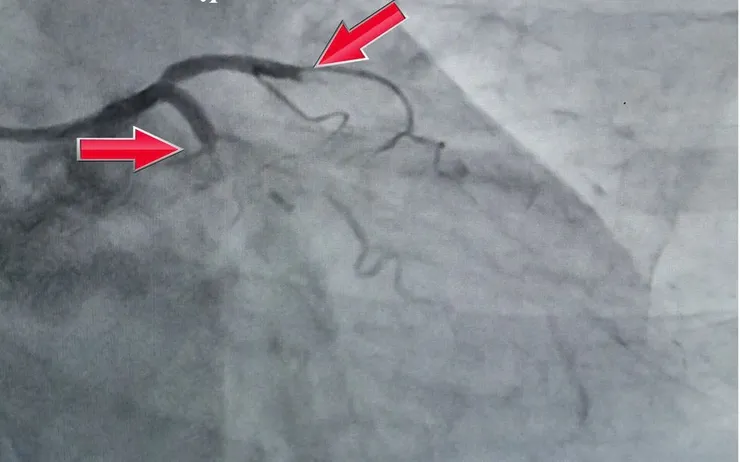

Kết quả chụp mạch vành ghi nhận tổn thương đặc biệt nặng: tắc cấp đồng thời hai nhánh chính động mạch vành - tình huống hiếm gặp, nguy cơ tử vong rất cao. Người bệnh được chỉ định can thiệp tái thông mạch vành khẩn cấp.

Sau nhiều phút nỗ lực liên tục, tim bệnh nhân đập trở lại, huyết áp dần ổn định. Ngay khi tuần hoàn tạm thời được duy trì, các bác sĩ tiếp tục can thiệp, đặt thành công 2 stent, tái thông hoàn toàn hai động mạch vành bị tắc, khôi phục dòng máu nuôi tim.